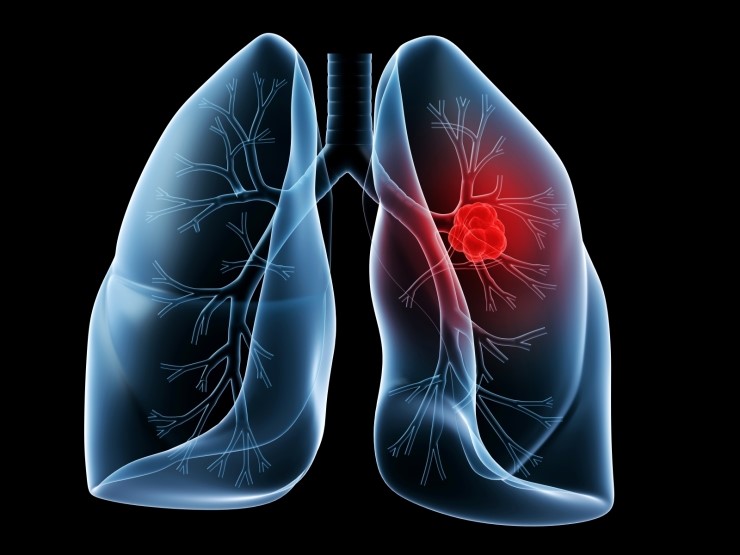

폐암은 원발성 폐암을 말하며 원발성 폐암은 폐에서 기원하는 악성 종양을 말한다. 폐로 전이된 암은 폐로 전이된 것으로 분류되며, 폐암이라기 보다는 기원 장기로 전이된 것으로 분류된다. 폐암은 조직학적 유형에 따라 크게 소세포폐암과 비소세포폐암으로 분류된다.

폐암의 초기증상 중에 흉통이 있습니다. 폐암 환자의 약 1/3이 흉통을 호소합니다. 흉통의 원인은 폐 가장자리에 종양이 형성되어 암세포를 생성하고 흉벽과 흉막에 침착되어 통증을 유발하는 것입니다.

흉통의 원인은 여러 가지가 있을 수 있지만, 오늘날 우리가 다루고 있는 폐암으로 인한 흉통은 경미한 통증보다는 지속적인 따끔거림과 둔한 통증을 동반한다는 점에 유의하시기 바랍니다. 또한 암은 흉막이나 흉벽 대신 갈비뼈로 퍼져 통증을 유발할 수 있습니다. 종양은 주변 조직 세포를 자극할 수 있으므로 계속해서 통증을 유발하는 경우 의사의 진찰을 받는 것이 좋습니다.